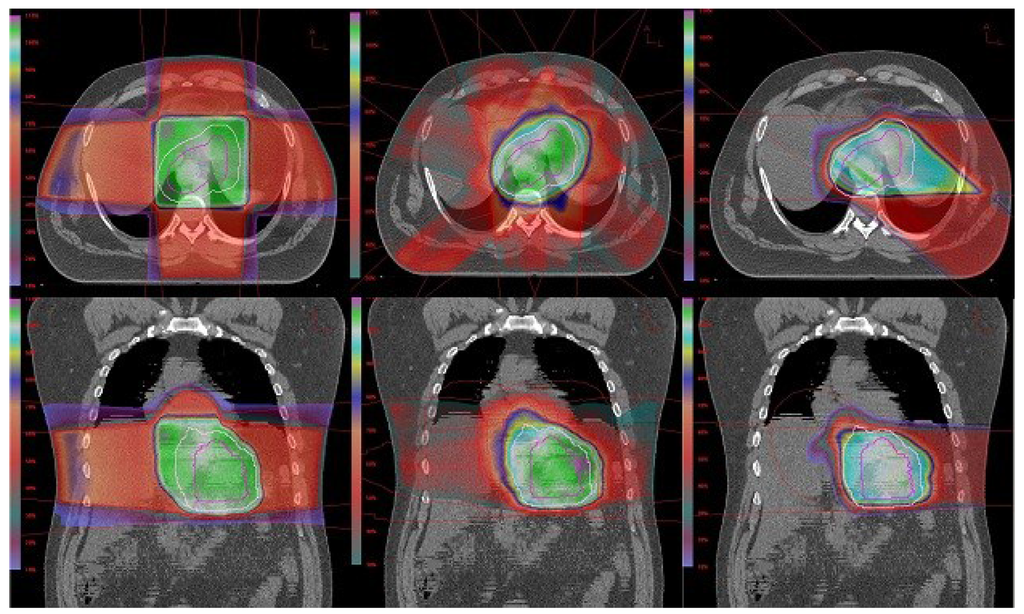

2.2. Simulation and Treatment Planning

2.3. Plan Evaluation and Analysis